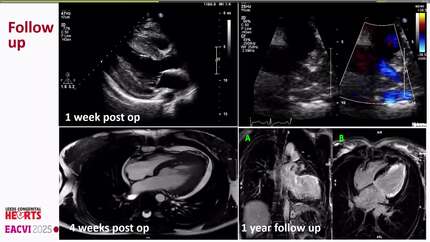

A rare case of left main coronary artery originating from the non-coronary sinus: a multimodality imaging-based assessment